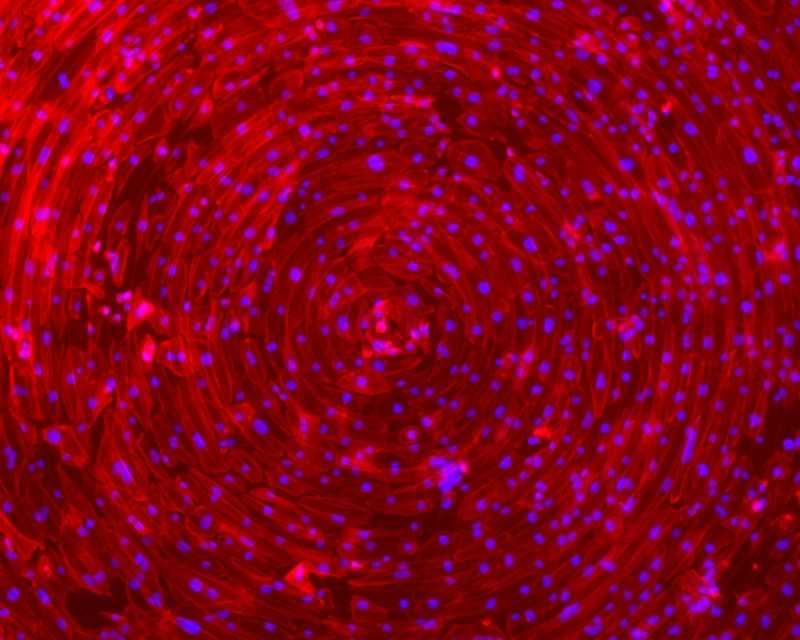

許聿翔表示,團隊研究心臟器官晶片,關鍵是心肌細胞培養,傳統培養皿作法,其細胞排序紊亂,跳動的同步性低,需好幾個月至半年,才能達模擬心跳的同步化,團隊透過溝槽結構與細胞力學,加上特殊基材,「騙」心肌細胞如在體內環境,僅14天到15天左右,就達同心圓收縮的同步化,可進行後續測試心臟藥物。

「機械也可結合生醫!」許聿翔說,該心臟晶片還結合壓電材料,讓心肌細胞跳動訊號直接轉成電訊號,讓心跳頻率免用高解析度顯微鏡觀察,直接用機器偵測心跳頻率,輸出心肌收縮波形,目前更搭配檢測業界的格式,已開發多孔盤自動化監測系統,有別其他晶片一次測1種藥,團隊設計一盤可塞3種藥,大幅提高新藥測試效率。